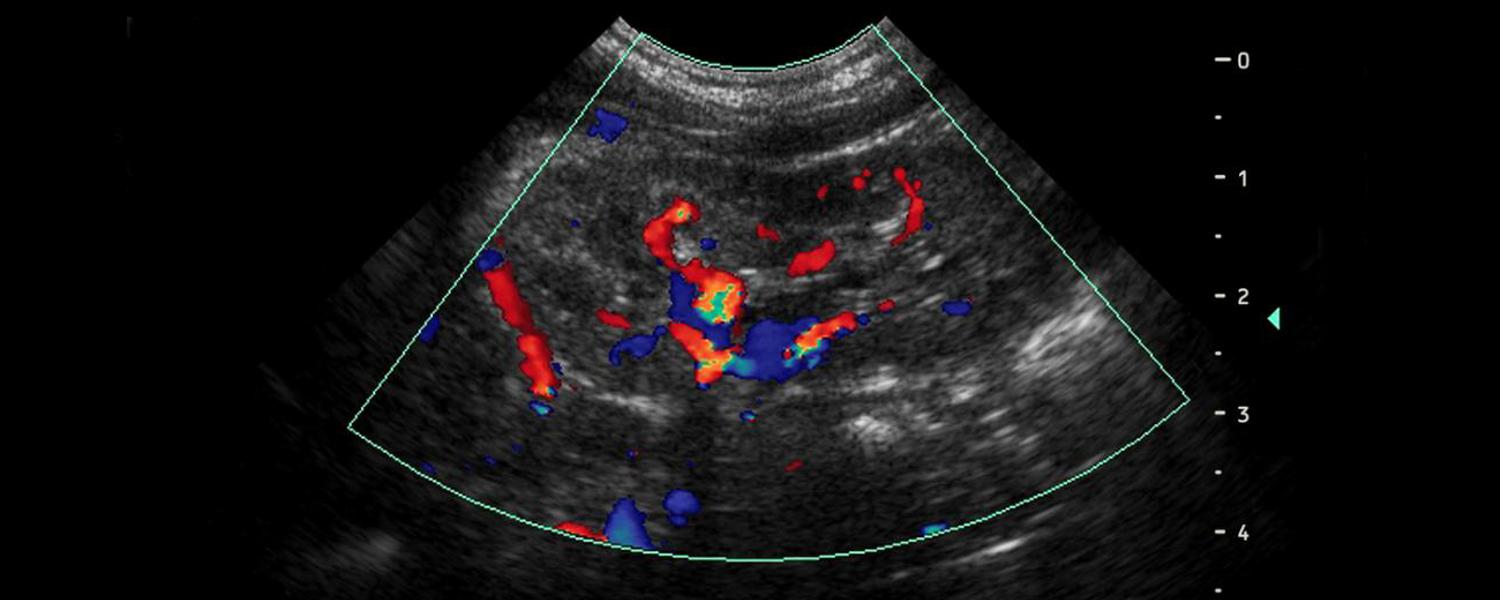

Es una técnica de imagen con la cual podemos explorar diversas estructuras del organismo gracias al uso del ultrasonido.

Los ecógrafos de última generación nos entregan imagenes con muy buena resolución, gracias a ello, no es necesario realizar exámenes de imagen directa como la laparoscopia o histeroscopia.